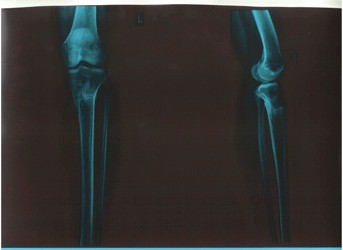

Рентгеновские снимки в 2 месяца после снятия аппаратов!

Вложения

рент.jpg

р-л.jpg